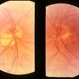

- inferior conus of optic nerve

- Fluorescein showing delayed filling in lower half, the area of conus.